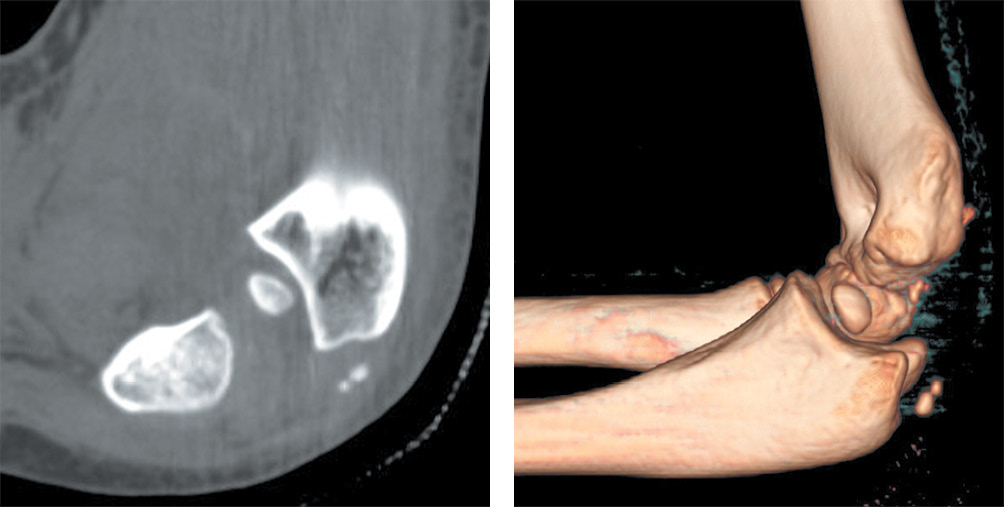

After approval of the study by the local ethics committee, the database of “Salesi” Children’s Hospital was mined for the records of all patients who presented to the Emergency Department (ED) with MEF from 1 January 2014 to 31 December 2017. The MEF were classified by an Orthopaedic surgeon, according with the classification described by Watson-Jones (WJ) [9] and reported by Papavasiliou [10]. The Inclusion criteria were MEF with intra-articular elbow entrapment, isolated (WJ type 3) or in association with elbow dislocation (WJ type 4). There were 13 children, 5 boys and 8 girls, whose mean age was 10.9 years (Range 8–13 years). Six patients reported a MEF with intra-articular elbow entrapment isolated (WJ type 3) and seven patients reported a MEF with intra-articular elbow entrapment after undergoing closed reduction for an associated posterolateral elbow dislocation (WJ type 4) (Fig. 1). Six patients presented with preoperative paresthesia in the ulnar nerve field. Standard anteroposterior and lateral plain films of the injured elbow were obtained at the ED. One patient receive a pre operatively 3D CT scan to confirm intra-articular entrapment (Fig. 2). All of MEF in our cohort were classified by an orthopaedic surgeon. The patients’ parents/guardians gave their informed consent to the use of the children’s medical charts. The mean follow-up was 24.1 months (range 11–44 months). The postoperative clinical evaluation was performed by the evaluation of the passive and the active range of motion (ROM), functional results using the Mayo Elbow Performance Score (MEPS) [11, 12], pain evaluated with the Visual Analogue Scale (VAS) [13]. The radiographic evaluation of fracture healing was performed on standard elbow X-ray after the removal of implants. All the surgical operations were performed by the senior Author (MM). For any patient, at final follow up, the evaluation of the deformity of the MEF after internal fixation was detected by Skak et al classification [14]. The complications were also reviewed (Table 1).

Fig. 2. Patient S. Post reduction CT-scan with 3D reconstruction shows ME intraarticular entrapment